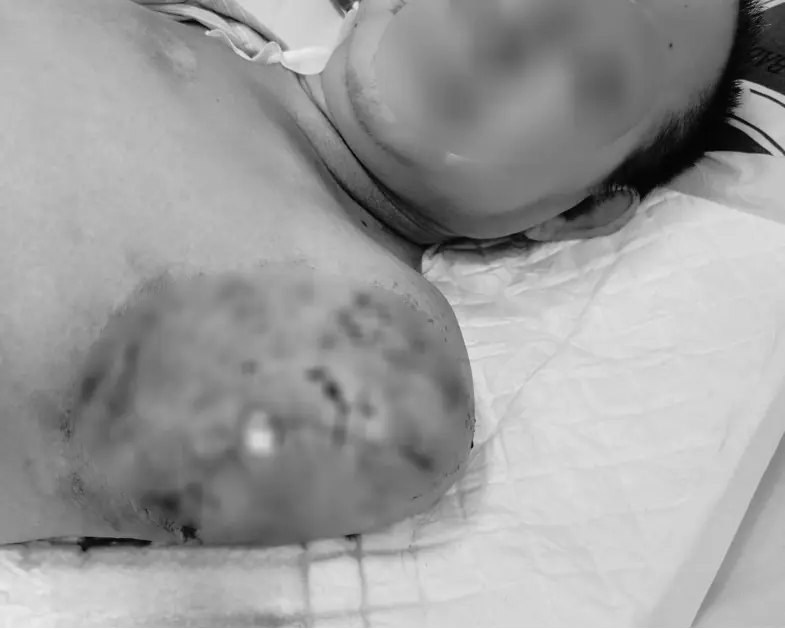

Nguồn cơn bắt đầu chỉ từ một vết mụn mủ nhỏ ở ngón tay trái. Người bệnh tự dùng kim chọc và đắp thuốc nam, lá cây. Chỉ sau hai ngày, toàn bộ tay trái sưng vù, xuất hiện nhiều phỏng nước máu, da tím đen, chảy dịch hôi. Nhiễm trùng lan nhanh, gây viêm mô tế bào hoại tử toàn bộ tay trái. Các chỉ số xét nghiệm đồng loạt báo động mức độ đặc biệt phức tạp và nguy kịch, tiên lượng tử vong rất cao. Mỗi giờ trôi qua là một giờ tử thần tiến gần hơn.

Ngày 26/11/2025, dù đã được hồi sức tích cực và lọc máu, tổn thương hoại tử tay trái tiếp tục lan rộng, trở thành ổ nhiễm độc khổng lồ giải phóng độc tố vào máu. Các chỉ số sinh hóa diễn biến xấu đi nhanh chóng. Bệnh nhân sốt cao liên tục, nhiễm trùng nặng, tiên lượng tử vong cận kề.